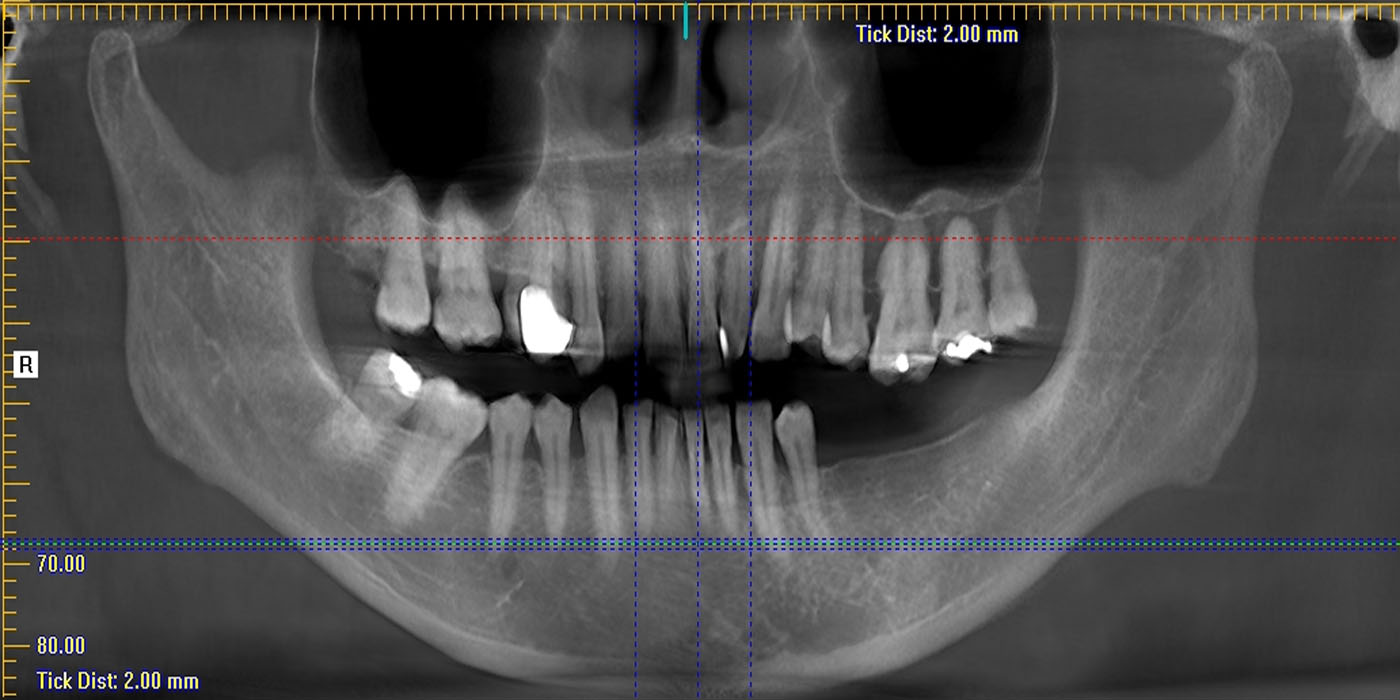

CBCT of the sinuses evaluate the paranasal sinus cavities – hollow, air-filled spaces within the bones of the face surrounding the nasal cavity. CBCT scanning is painless, noninvasive and accurate. It’s also the most reliable imaging technique for determining if the sinuses are obstructed and the best imaging modality for sinusitis and other problem related to sinus.